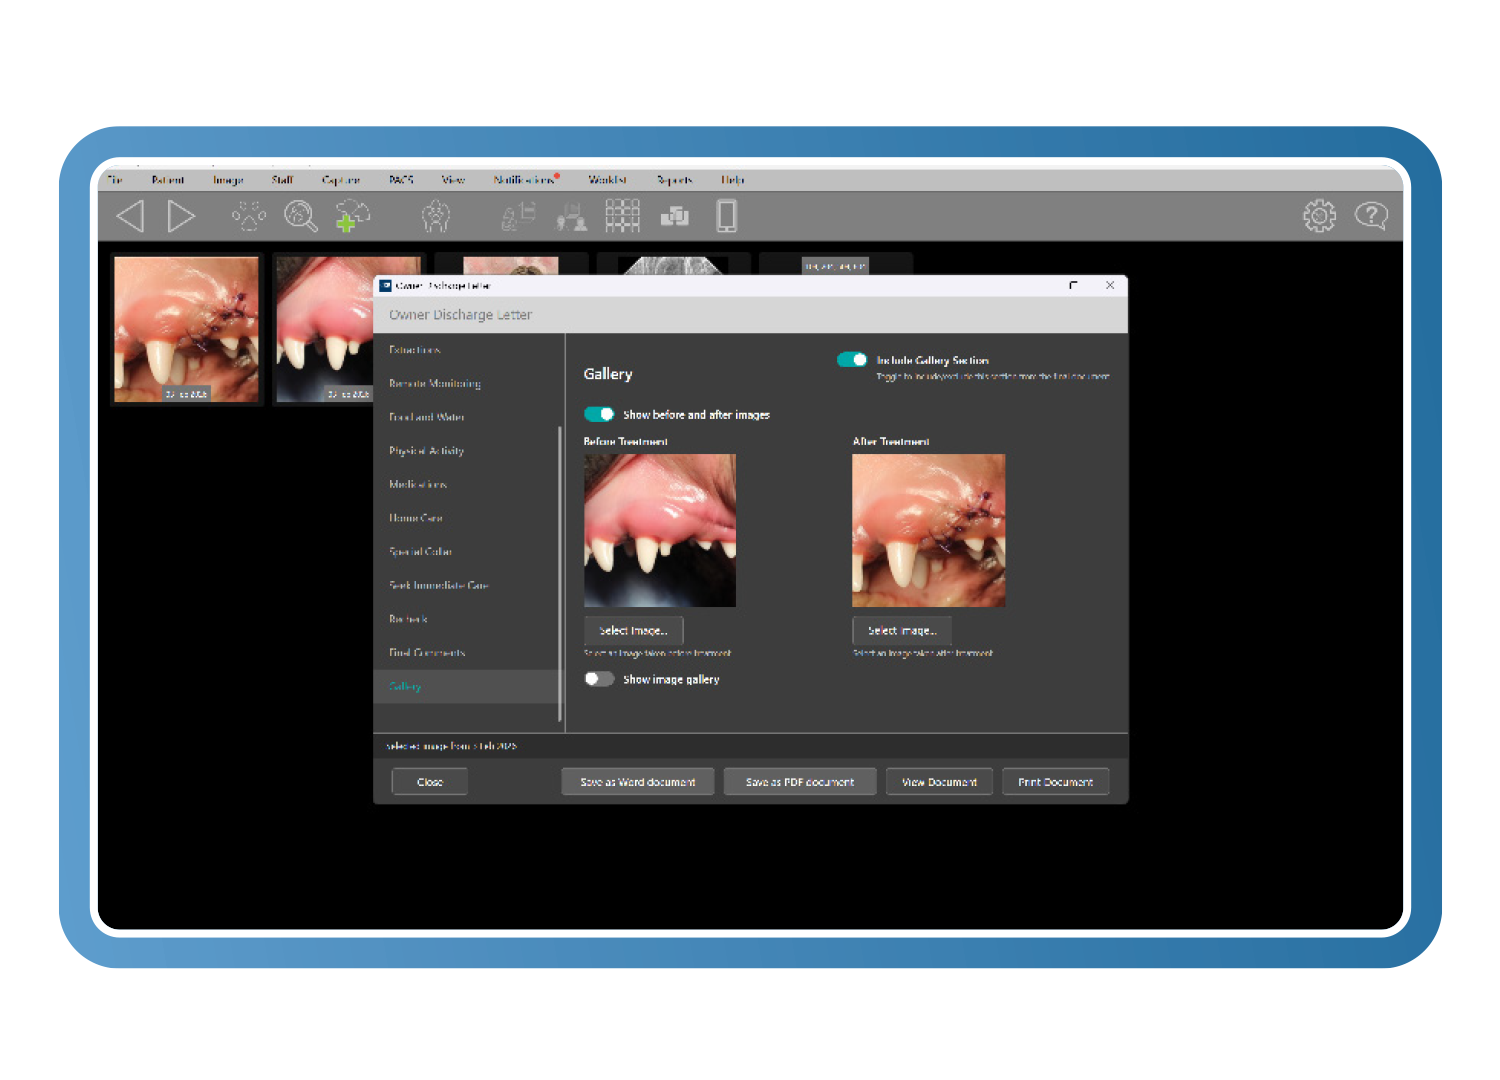

Alta clínica y monitoreo remoto según mejores prácticas

Cree cartas de alta personalizables alineadas con las directrices de la AAHA, que incluyen explicaciones en lenguaje claro, imágenes de antes y después y contenido asistido por Clarity. El monitoreo remoto de heridas integrado permite a los propietarios enviar imágenes después del tratamiento, reduciendo las revisiones innecesarias mientras se mantiene la supervisión clínica.